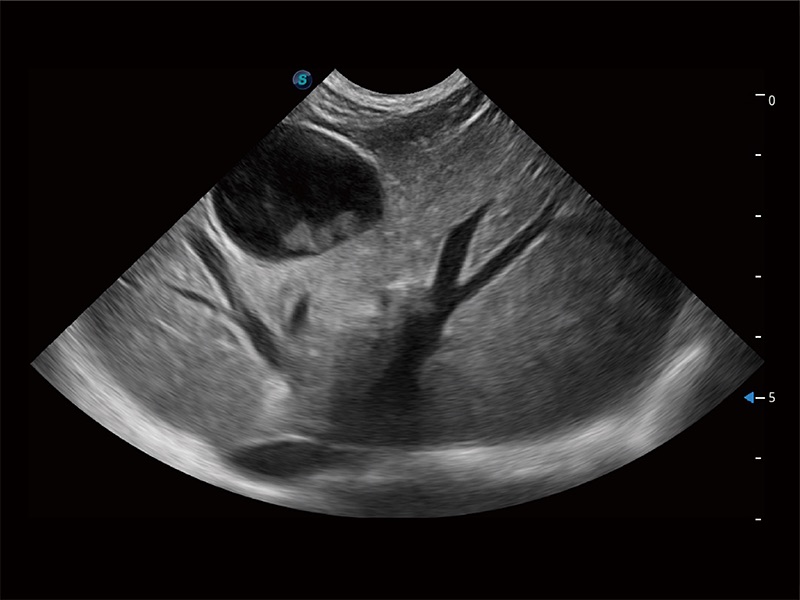

ProPet 80 配备了丰富的心脏探头群、先进的成像技术和专业的心脏测量工具,可帮助动物医生为不同体型和生理结构的动物提供心脏和心肌功能的全面评估。

高性能和先进的临床应用工具可以为动物医生提供临床信心。ProPet 80 搭载了先进的腹部和浅表应用工具,帮助医生在日常临床实践中发挥前所未有的作用。